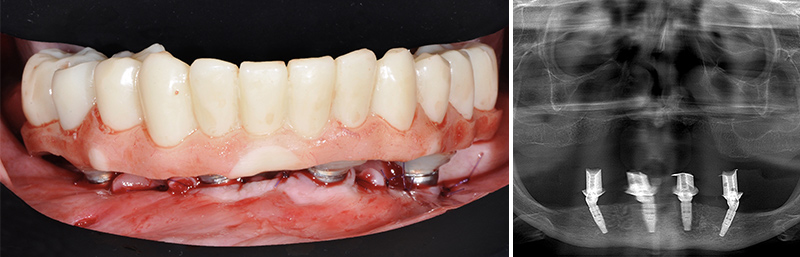

Fig. 51 : les dents sont extraites sans lambeau par fractionnement puis le guide de résection osseuse est inséré et claveté dans les emplacements précédemment forés.

Fig. 52 : le guide de forage et de mise en place des implants est empilé sur le guide de résection osseuse.

Fig. 53 : vissage des piliers prothétiques dans les implants.

Fig. 54 : transvissage des gaines temporaires sur les piliers.

Les piliers prothétiques sont immédiatement vissés dans les implants sans déposer le guide de résection osseuse ; des gaines temporaires en titane sont transvissées sur les piliers et la restauration transitoire empilée sur le guide de résection, pour être solidarisée en bouche avec une colle composite. La finition très simple est réalisée au fauteuil et le patient quitte le cabinet dès la fin de la chirurgie avec sa restauration provisoire.

Fig. 55 et 56 : restauration provisoire terminée.